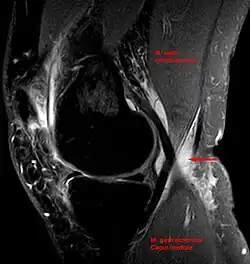

A specimen from a cadaver of a Baker's cyst in popliteal space -

Baker's cyst on axial MRI with communicating channel between the semimembranosus muscle and the medial head of the gastrocnemius muscle. -